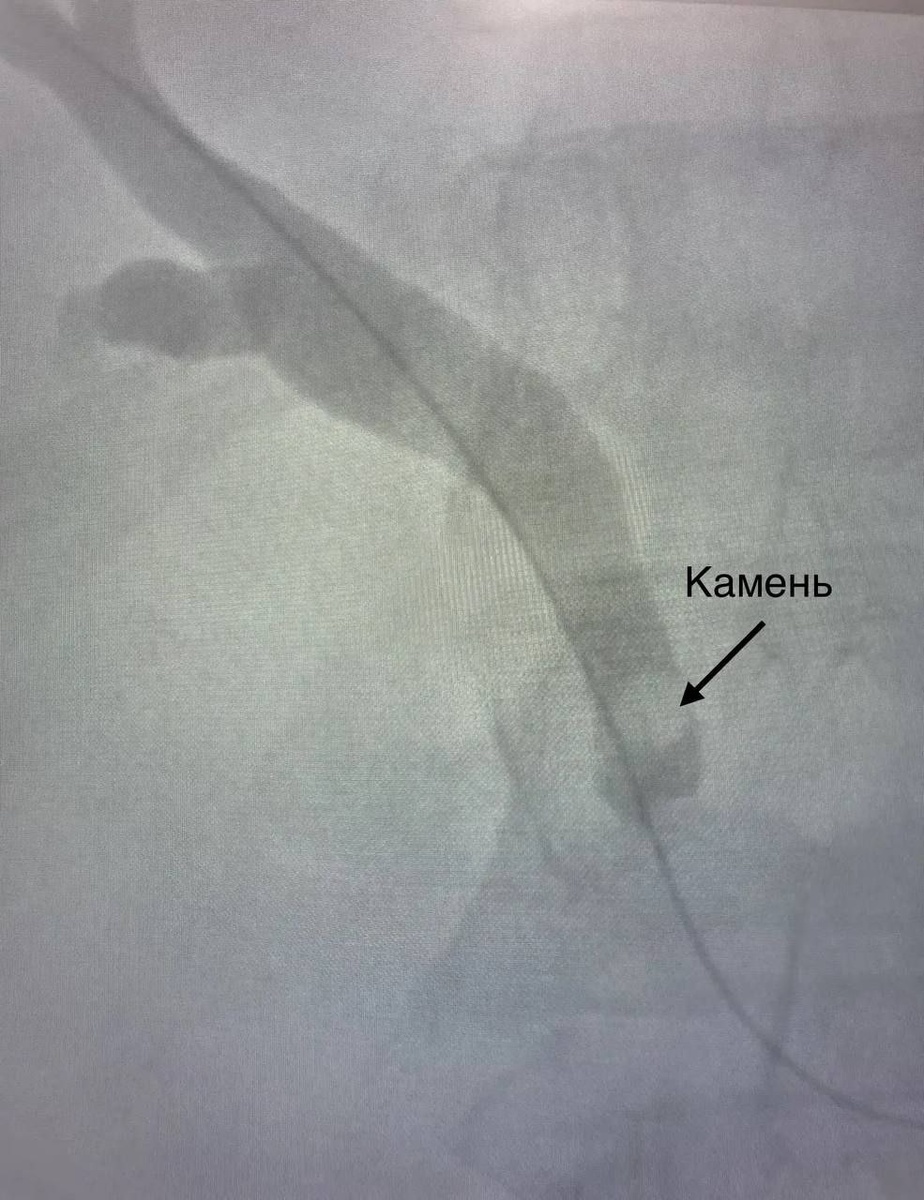

Редкую операцию провели хирурги БСМП имени Акчурина. Методика была применена в больнице впервые

У 55-летнего пациента из-за застрявшего в желчном протоке камня развилось жизнеугрожающее состояние. Отток желчи прекратился, из-за чего развилась сильная желтуха. Достать камень эндоскопически оказалось невозможно: мешало образование (дивертикул), которое препятствовало безопасному выполнению процедуры. Мужчину ждала большая полостная операция с долгим восстановлением и заживлением послеоперационной раны.

Но врачи БСМП нашли другой выход. Под контролем рентгена хирурги провели миниинвазивную операцию. Через маленький разрез пациенту ввели проводник, через который хирурги с помощью инструментов выполнили удаление камня.

«Через протоки печени мы ввели специальный инструмент в виде петли, захватили камень и достали его, используя жесткий тубус. Действовать нужно было аккуратно, просчитывая каждый миллиметр, в этом и была сложность. Подобную операцию мы проводили впервые, все прошло успешно. Пациент все время был в сознании, под местной анестезией» - Зоя Антропова, рентгенхирург.